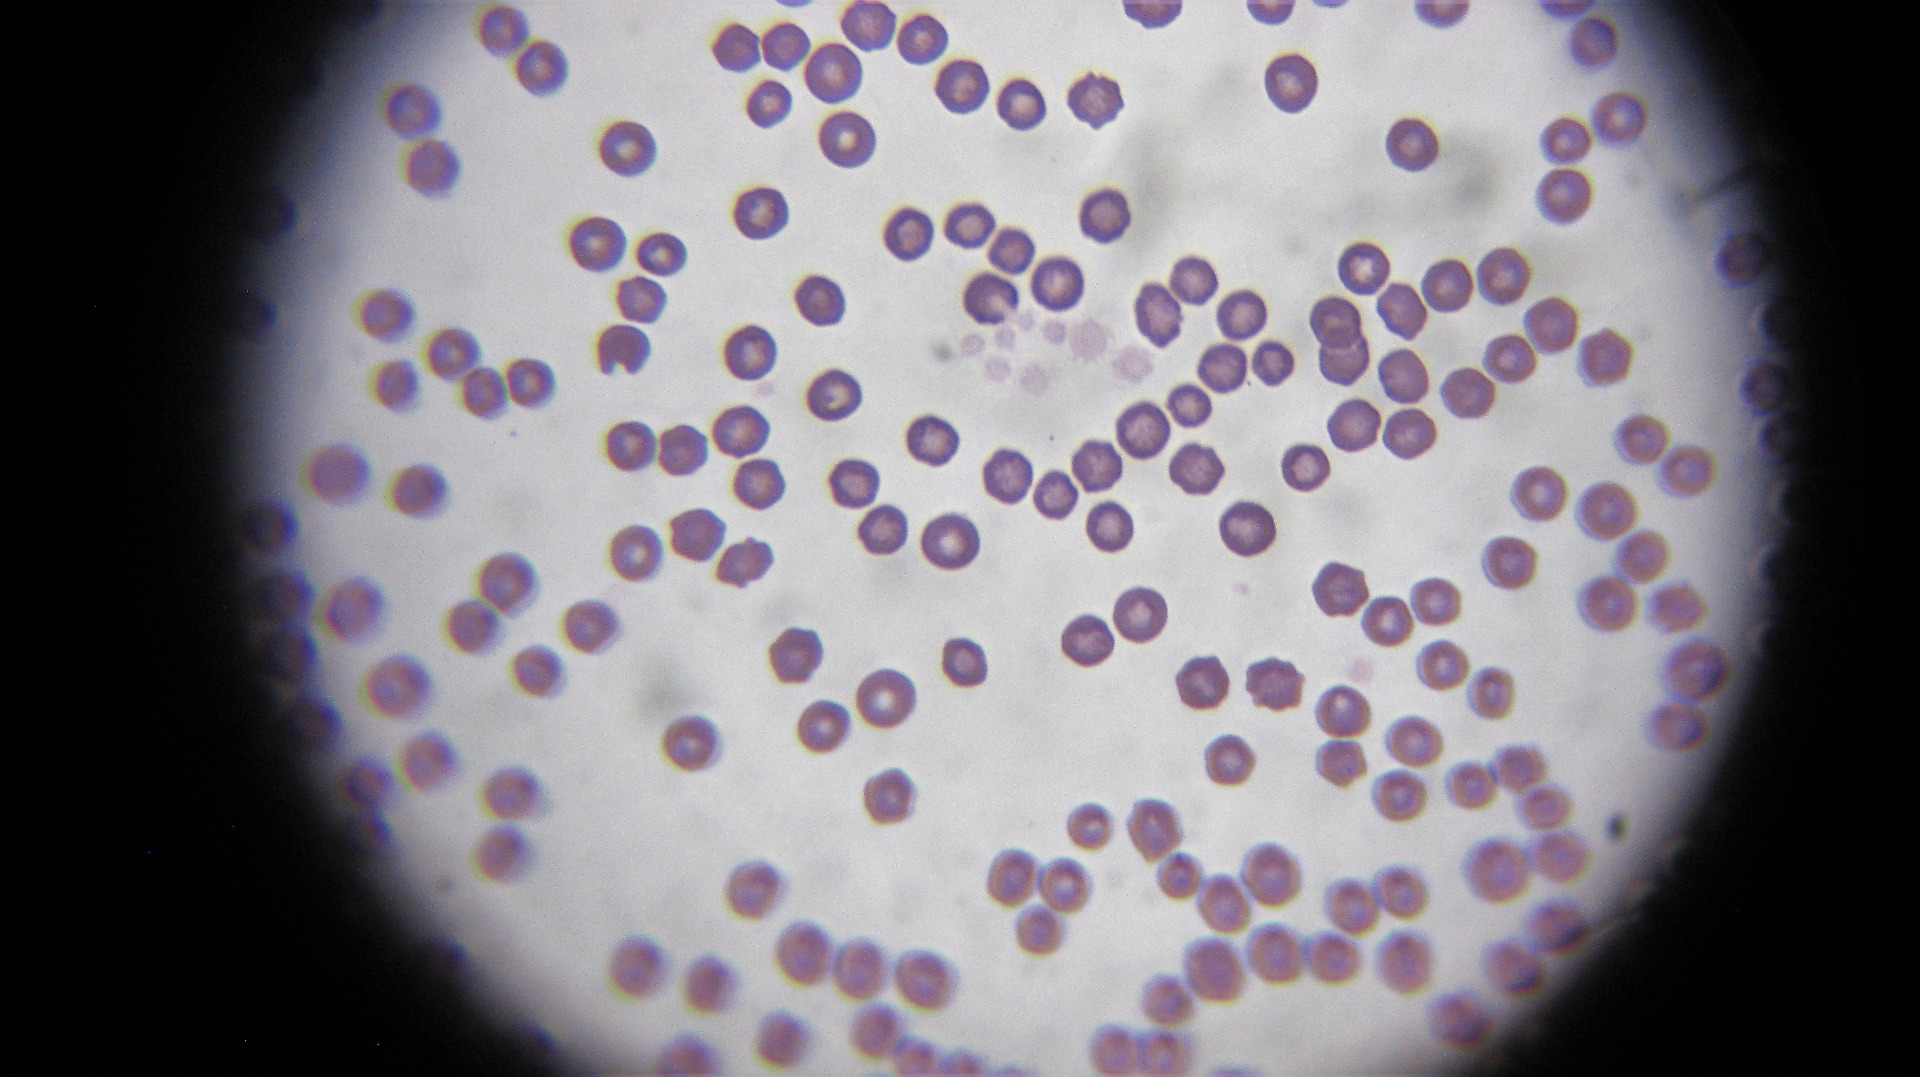

laboratórne vyšetrenie krvi, moču, trusu, cytológia